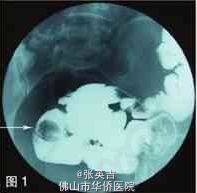

患者生命体征平稳,营养良好。心肺(-),腹软,脐右深压痛,无反跳痛、肌紧张,肠鸣音亢进,未及包块。 妇科B超检查提示:子宫双附件未见明显异常。 全消化道造影提示:远段回肠占位病变(图1)。 腹部盆腔增强CT及小肠重建检查提示:在右下腹,肠腔内有占位,考虑息肉致肠套叠的可能性大,局部系膜血管影增多,周围有大量渗出影及小淋巴结(图2、3)。